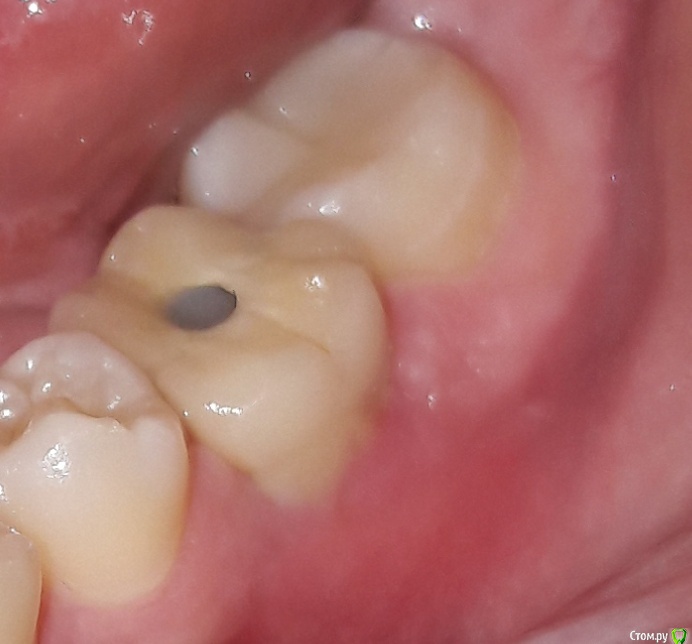

anasta.siiia1 Опубликовано 12 апреля, 2019 Поделиться Опубликовано 12 апреля, 2019 Здравствуйте всем! Поставили коронку 1 неделю назад. Между коронкой и десной забивается вся еда, которую я ем.(Овощи, фрукты, мясо и т.д). Именно со стороны щеки. Зуб 6-ой нижний слева.Ходила к своему стоматологу-ортопеду, сказал что ничего страшного в этом нет, это совершенно нормально, проблема решается зубной нитью, и плюс посоветовал преобрести ирригатор, проблем с десной нет и т.д и т.п. Так вот нитью я ничего не могу оттуда толком достать,только острым краешком зубочистки. И еда забивается настолько, что достовляет дискомфорт. Ощущения прям такие, как будто бы десна чем-то забилась плотно. Целую неделю так и живу с этим зубом, достаю эти куски еды. Даже щеткой не прочистишь. Ну и запах конечно от застрявшей еды, просто жесть...((( Буквально вчера воспалилась десна и идет гной оттуда... Ссылка на комментарий

krokomot Опубликовано 13 апреля, 2019 Поделиться Опубликовано 13 апреля, 2019 в области коронки с щечной стороны в пришеечной области отсуствует прикрепленная десна, её необходимо сформировать, делает это хирург-стоматолог владеющий пластикой десны. Коронку снять, провести пластику десны с формированием правильного контура и массива прикрепленной десны и будет вам счастье, снимок сделать и приложить к теме. Ссылка на комментарий